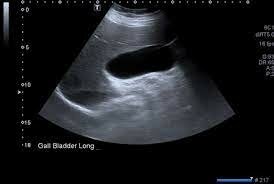

• Ian Donald /OBGYN

Ian Donald /OBGYN

Donald incorporated ultrasound into the OBGYN field of medicine. The ultrasound image of a female genital tumor. Dr. Tom Brown invented the so-called “two-dimensional compound scanner”, which enabled the examiner to visualize the density of the tissue.